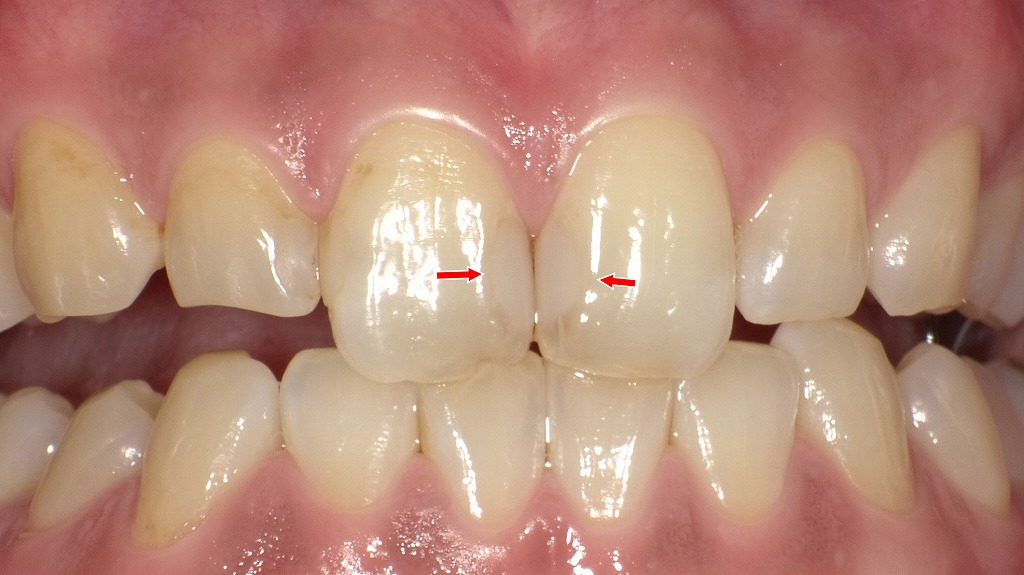

コンポジットレジン充填直後

前歯の小さな虫歯による欠けをコンポジットレジンで精密に修復。色調・透明感・形態を細かく調整することで、充填部の境界が見分けにくいほど自然に仕上がっています。